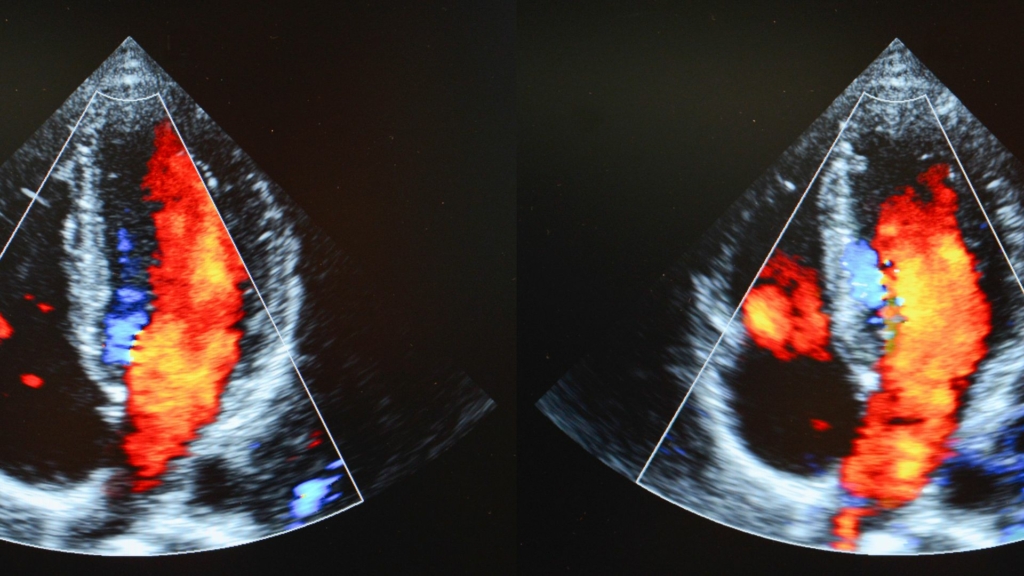

- การตรวจสมรรถภาพหัวใจด้วยการวิ่งสายพานหรือการตรวจภาพคลื่นเสียงสะท้อนหัวใจ